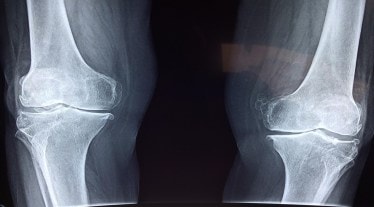

Osteoporosis, also referred to as a ‘silent’ illness, frequently goes unnoticed until a bone is broken. According to data, 20% of the 230 million Indian women over age 50 have osteoporosis. Moreover, prevalence of osteoporosis ranging from 8 to 62% in Indian women of different age groups has been reported in several studies. Among other reasons, rapid urbanization leading to sedentary lifestyle, increased indoor living and reduced exposure to sunlight are the contributors to increased cases of osteoporosis. It makes women susceptible to fractures as density of bone decreases and production of new bones become insufficient.